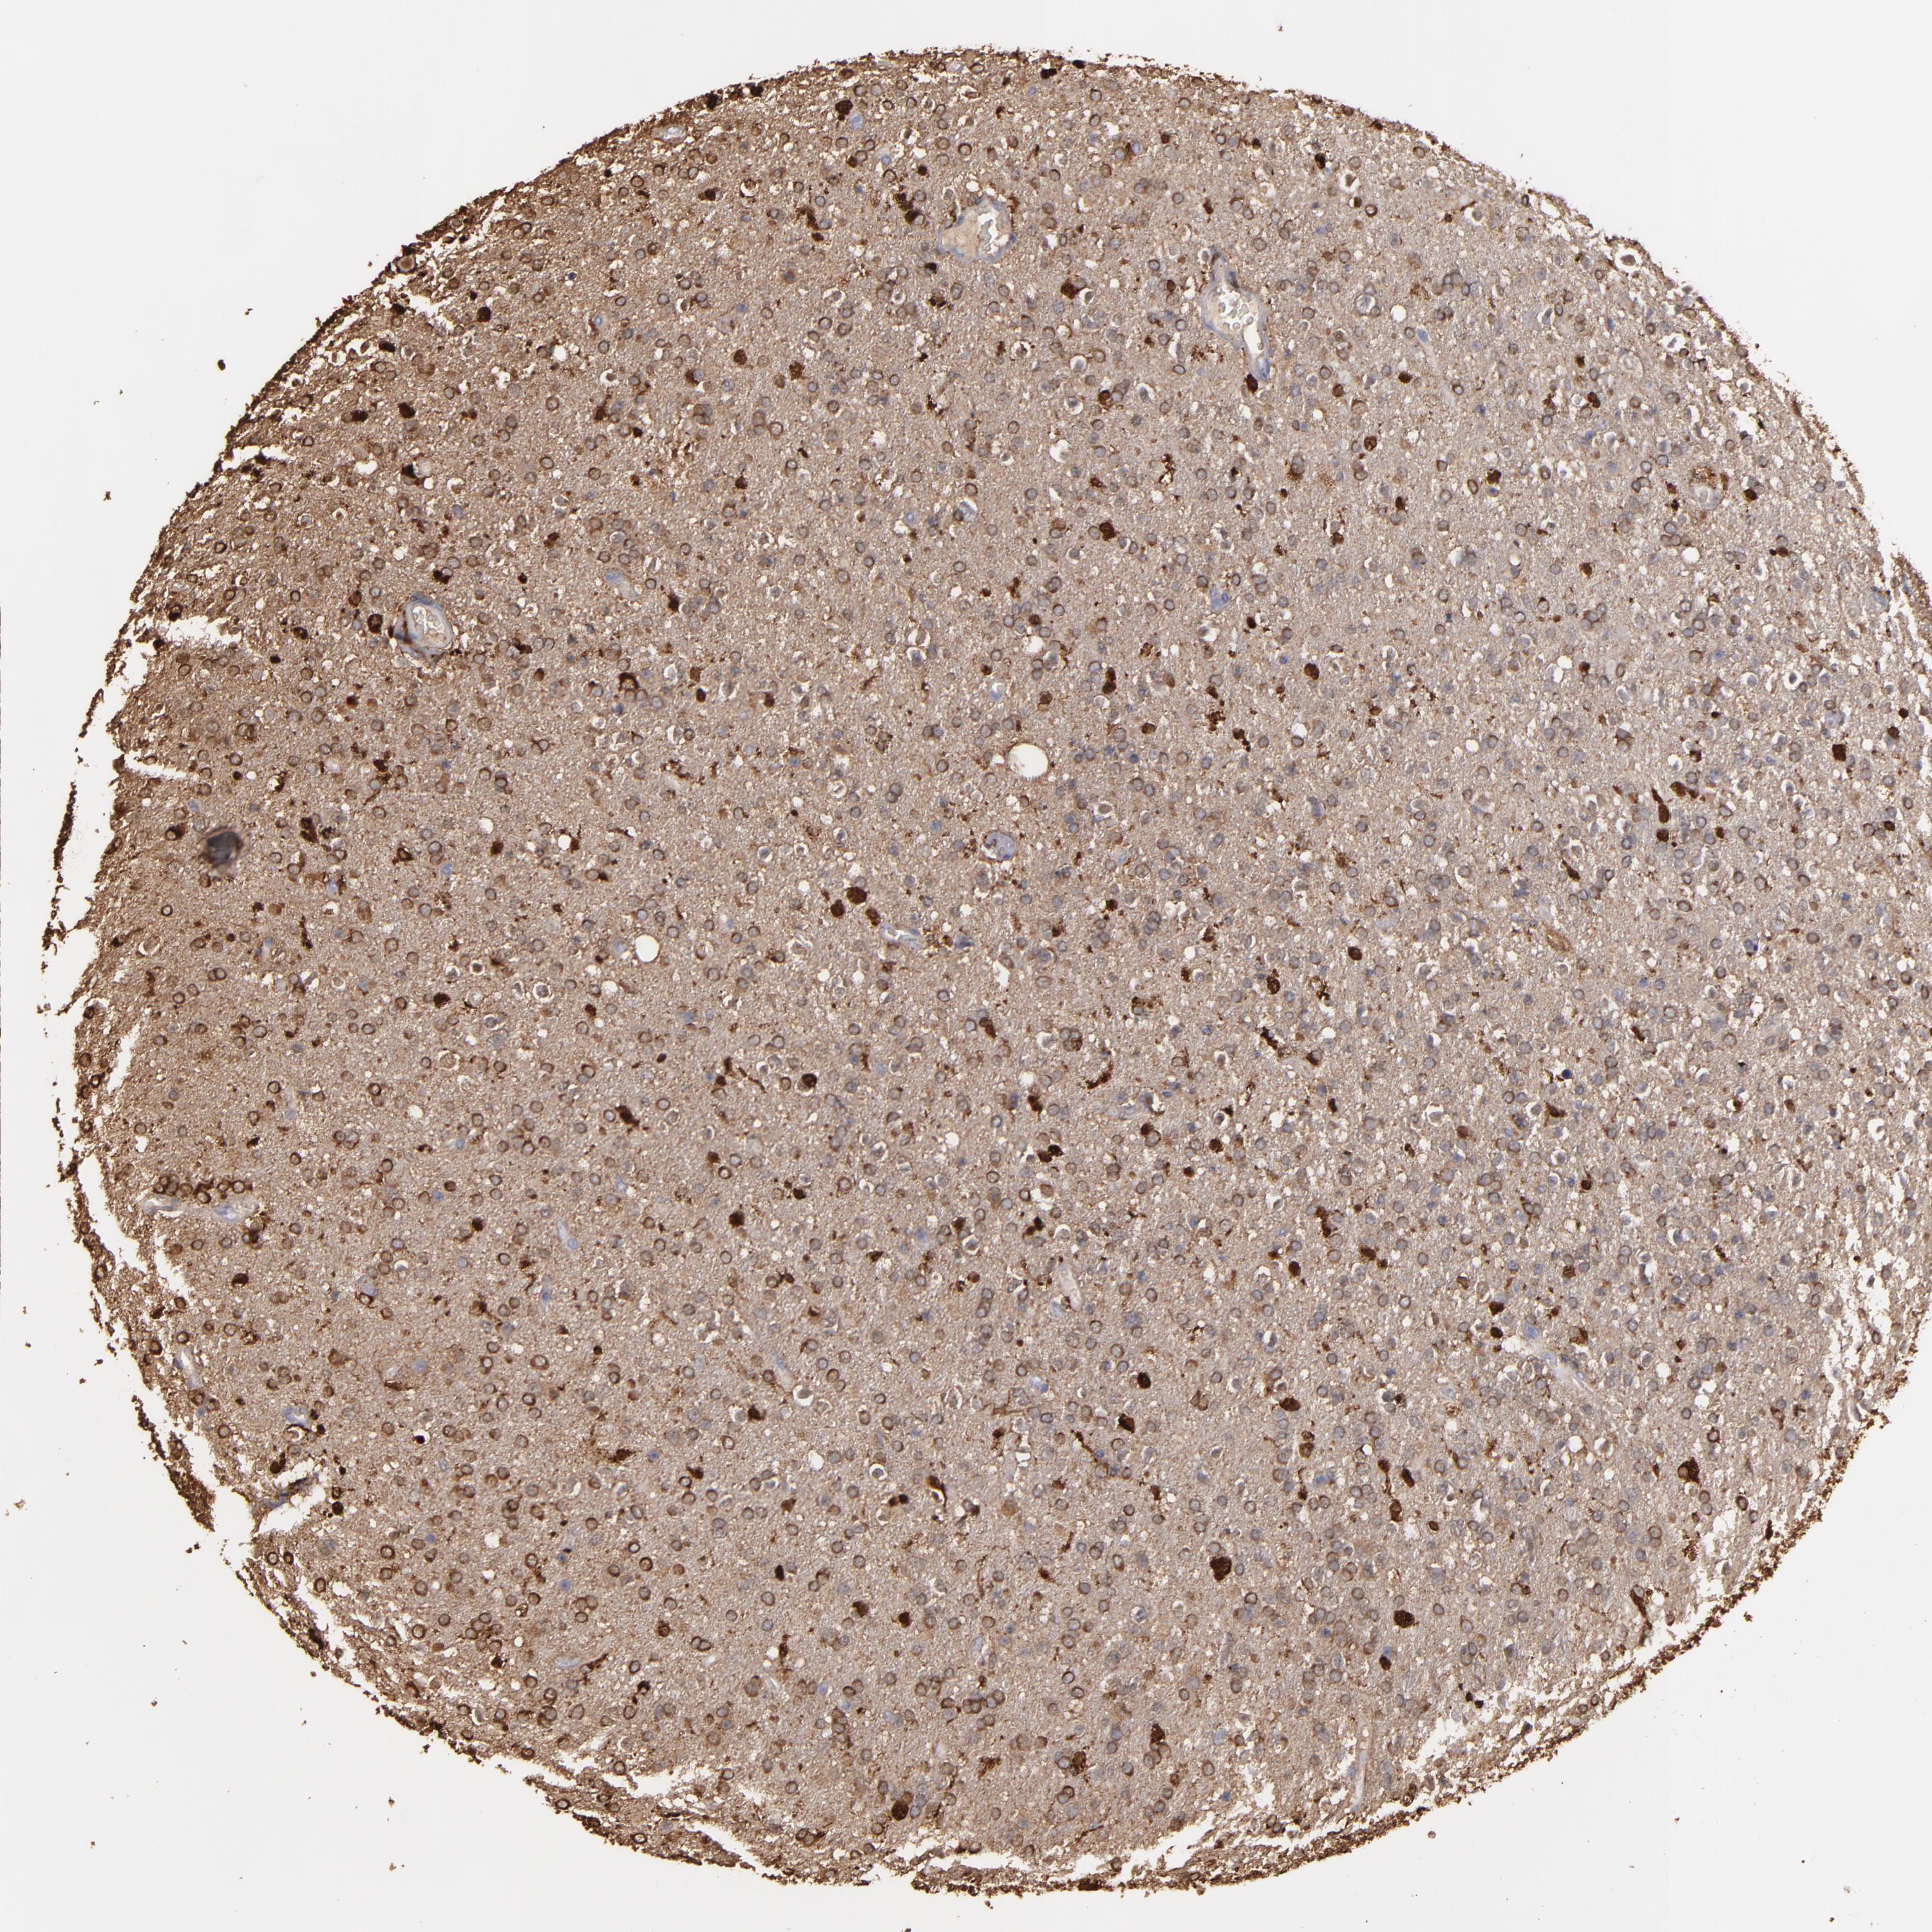

GLIOMA - Protein expressioni

A mouse-over function shows sample information and annotation data. Click on an image to view it in a full screen mode. Samples can be filtered based on level of antibody staining by selecting one or several of the following categories: high, medium, low and not detected. The assay and annotation is described here.

Note that samples used for immunohistochemistry by the Human Protein Atlas do not correspond to samples in the TCGA dataset.

Antibody stainingi

Antibody staining in the annotated cell types in the current human tissue is reported as not detected, low, medium, or high, based on conventional immunohistochemistry profiling in selected tissues. This score is based on the combination of the staining intensity and fraction of stained cells.

Each image is clickable and will lead to virtual microscopy that enables deeper exploration of all samples and also displays staining intensity scores, fraction scores and subcellular localization as well as patient and tissue information for each sample.

Antibody HPA001536

Antibody CAB035996

Staining

High

Medium

Low

Not detected

Intensity

Strong

Moderate

Weak

Negative

Quantity

>75%

75%-25%

<25%

None

Location

Nuclear

Cytoplasmic/membranous

Cytoplasmic/membranous,nuclear

Glioma, malignant, High grade

Glioma, malignant, Low grade

Glioma, malignant, NOS

Glioblastoma, NOS